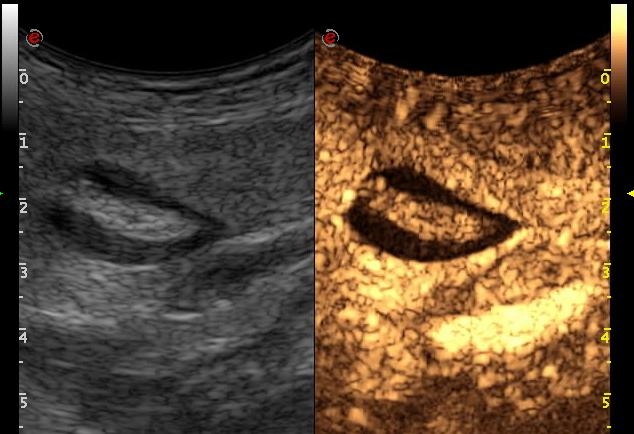

| a műtét utáni UH-vizsgálat a v. umbilicalis tágulatát mutatja szabályos áramlással |

| natív mérés |

| coronalis recon (az elváltozás körbeveszi a ligamentumot) |